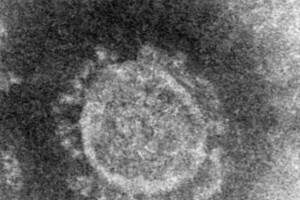

情報が日々更新され、対応に追われる新型コロナウイルス禍。厚生労働省のクラスター(感染集団)対策班の押谷仁・東北大教授(ウイルス学)が今後の対策方針を示した資料が「非常にわかりやすい」「当面は行動を変えよう」とSNS上で反響を読んでいる。押谷氏はJ-CASTニュースの取材に、感染拡大を防ぐためには「全世代」で当事者意識を持つべきだと話す。爆発的感染以前に「医療崩壊」の懸念も押谷氏は2020年3月29日、新型コロナの拡大防止に向けたこれまでの取り組みと今後の方針を整理した資料「COVID-19への対策の概念」の暫定版を公開した。主な内容は次の通り(※J-CASTニュース編集部で、4月1日までにわかった情報を補足しています)。2003年の重症急性呼吸器症候群(SARS)では、ほぼすべての感染者が重症化したため、すべての感染連鎖を見つけて断ち切ることで封じ込めに成功した。一方、新型コロナは多くの感染者が無症状か軽症で、すべての感染連鎖を見つけることは「ほぼ不可能」だと説く。全体像をつかむには、国民の大半がPCR検査を受けなければならず、医療供給体制などの面から現実的ではないという。政府の専門家会議は4月1日、すでに供給がひっ迫しつつある地域が出てきており、爆発的感染(オーバーシュート)が起こる前に「医療崩壊」に陥る懸念を示している。押谷氏によれば、日本は現在、感染流行の"第二波"のまっただ中にある。中国湖北省を発端とした"第一波"では、「保健所・自治体・地方衛生研究所・感染症研究所・検疫所・クラスター対策班の若手研究者などの努力でなんとか乗り切ってきた」ものの、第1波の流行の残りに加え、3月以降に海外からの感染流入が激増したため、新たな波が起きたと考えられる。日本は「中国&シンガポール」モデルで対策現時点で感染は施設内が多く、爆発的に地域内感染が増えている状況ではない。しかし、感染者、孤発例(感染経路が追えない症例)ともに着実に増えており、押谷氏は「ぎりぎりの状態にある」と警戒する。大規模な地域内流行が起こる条件は、▽クラスターの連鎖発生▽大規模クラスターが生まれ、そこから多くのクラスターに派生――の2点だ。押谷氏は「感染者」「接触者」「感染連鎖」「クラスター連鎖」を制御できれば防げるといい、具体的には以下の状況を作るのが望ましいとする。・感染者:入院措置もしくはそれに準ずる措置・接触者:14日間健康監視の徹底・感染連鎖:医療機関・高齢者施設での積極的疫学調査・クラスター連鎖:感染源の大半が追えて周囲にクラスター形成がない状況クラスター対策班としては、都市封鎖と外出禁止令でウイルスをほぼ完全に制御した中国と、感染連鎖をほぼ完全に可視化して感染流行の第一波を制御したシンガポールを参考に、日本独自の対策づくりを目指している。目標を「感染の拡大のスピードを抑制し、可能な限り重症者の発生と死亡数を減らすこと」と定め、対策の柱に「クラスターの早期発見・早期対応(断ち切り)」「患者の早期診断、重症者への集中治療の充実と医療提供体制の確保」「市民の行動変容」の3本を掲げる。現時点で「中国での経験からも、接触機会を減らすことで大規模な流行も収束させることが十分に可能」との評価だ。若年層クラスターを「見える化」するには「『武漢市を含む湖北省への渡航歴があり、発熱かつ呼吸器症状を有する人』との接触歴がある」などを条件に発生動向調査(サーベイランス)を進めると、2月13日に突然、感染連鎖が見えてきた。しかしこの段階ですでに連鎖が各地で進んでおり、全体像の把握は困難だったと振り返る。「突然見えた感染連鎖(2月13日)」(押谷氏の資料より)クラスター対策班で見つかった感染経路を掘り下げると、感染者との濃厚接触者からは二次感染が出ていないことがわかった。一人の感染者が何人に感染を広げるかを指す指標「R0(基本再生産係数、アールノート)」ではR0=0となる。「基本再生産計数」(押谷氏の資料より)「1人の感染者が生み出す2次感染者数の頻度」(押谷氏の資料より)それではなぜ流行しているのか。「多くの人は誰にも感染させないが、一部に1人が多くの人に感染させていると考えないと流行が起きている理由を説明できない」ため、感染源(リンク)の追えない症例からつながった患者のうち5人以上の集団を「クラスター」と定義し、「早期発見・早期対応」を目指した。クラスターさえなければR0<1、つまり感染者が出ても流行にはならないからだ。※東京都の推定値はR0=1.7(3月21〜30日の期間)「クラスターが起きなければ」(押谷氏の資料より)ただし、クラスターの早期発見は容易ではない。特に、若年層(10代後半〜50代と独自定義)は重症化することが少なく、「若年層クラスター」の連鎖は見えづらい(「アクティブな中高年からなるクラスターも数多く見られている」とも注記している)。若年層クラスターを「見える化」するには、「若年層クラスター連鎖から高齢者に漏れ出した場合」「まれにおこる若年層での重症例が出てきた場合」「軽症者がなんらかのきっかけで検査を受けた場合」のいずれかだという。「夜の街」クラスターが見えにくい理由クラスターをめぐる問題で、最近新たに分かったことがある。押谷氏は、若年層クラスターは「生物学的理由」で見つけづらかったが、密接な接触を伴う飲食店に関連するクラスターは「社会的理由」で見えにくいという。その結果、クラスター連鎖を見つけられず、病院や高齢者施設の流行につながっている可能性を指摘する。大阪府の吉村洋文知事は4月1日の記者会見で、クラスター発生が疑われるナイトクラブやバーの調査は「非常に困難を極めている。調査は結局、関係者、陽性者に聞き取るしかない」と協力が得られず、実態解明が進んでいないと明かした。店名公表を拒否されるケースもあり、吉村知事は「ナイトクラブや夜の接客を伴う飲食店に行かれ、症状が出た方はすみやかに保健所に相談してほしい」と呼びかける。資料は最後、より厳しい第2波を乗り切るための「お願い」として、「保健所・地方衛生研究所・検疫所・クラスター対策班の人員の早急な拡充。特に保健所の負担の軽減」「日本に住むすべての人が、この問題を真摯に考え、それぞれの行動を見直してもらうこと」を訴えている。「行動変容、行動変容、行動変容!」資料からは、国や医療従事者の努力だけでは不十分で、国民の協力が不可欠とのメッセージが伝わってくる。「行動変容、行動変容、行動変容!」と強く呼びかける記述もあった。押谷氏は4月1日のJ-CASTニュースの取材に、その意図を「みんなで日本を守る意識がないと戦えない。それぞれの世代がそれぞれの役割を持っている」と話す。「みんなが対立して、中高年が俺は構わないと居酒屋やカラオケに行ったり、若い人は自分たちは重症化しないと思ってライブハウスにいくといったことを繰り返すと、ヨーロッパやニューヨークで見ていることが日本でも起こるかもしれません。それでいいんですかってことです。日本で死者が累々と出て、その責任は誰が取るのか。自己責任じゃないですよね、これ。だからみんなでやらないといけない。みんなで協力しないとこの感染症は止まらない。だから対立したら駄目なんですよ。国が対立してもだめ、世代間で対立してもだめ。自己責任が取れる感染症ではないのですから」(押谷氏)「3つの密」(密集、密着、密閉)が重なる場を避けたり、手洗いや咳エチケットだったりと、基本的な感染対策の徹底が求められる。資料はhttps://www.jsph.jp/covid/files/gainen.pdfから閲覧できる。(J-CASTニュース編集部 谷本陵)